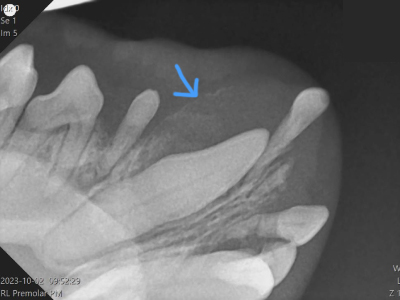

下側が右下顎で大きな犬歯が存在しています。歯冠部外側(↑矢印部)の骨は大きく膨らみペラペラになっています。

-

角度を変えた撮影でも歯冠部周辺に風船のように膨らんだ薄い骨が確認できます。(↑矢印部)

かなり変化していますが骨折を引き起こす前に抜歯することが出来ました。